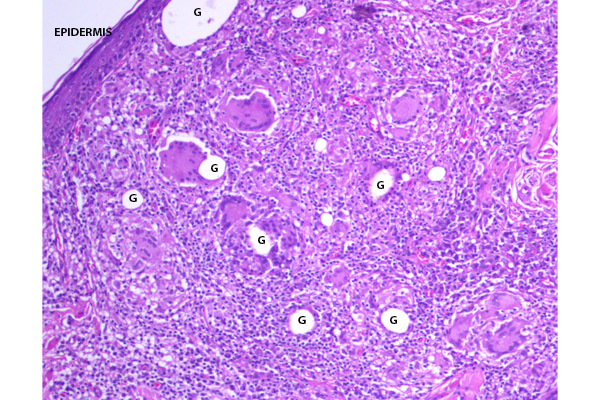

En un corte histológico del párpado se aprecia un granuloma compuesto principalmente por células epitelioides y células gigantes.

Los granulomas se distribuyen difusamente, alterando la histología del párpado.

Presencia de granulomas en la dermis superficial y profunda.

La reacción inflamatoria rodea los anexos pilosos y las glándulas de Moll, alcanzando la capa muscular.